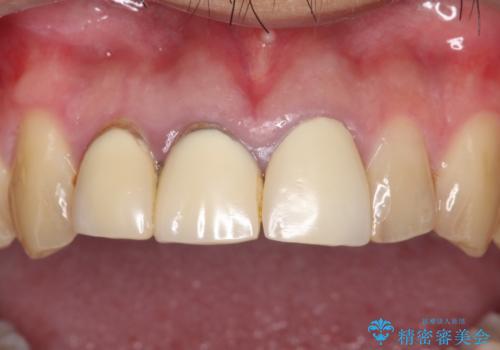

土台からの、再治療を行い、オールセラミッククラウンの装着を行う計画としました。

審美的な改善はもちろんのこと、ぴったりとしたものを装着することで、歯茎の発赤も改善されました。